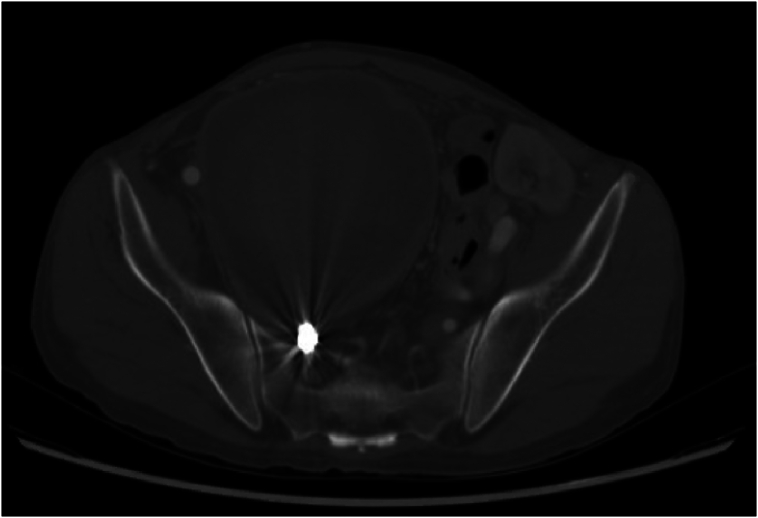

Fig. 3.

Increase in the size of the previously excluded right internal iliac artery aneurysm.